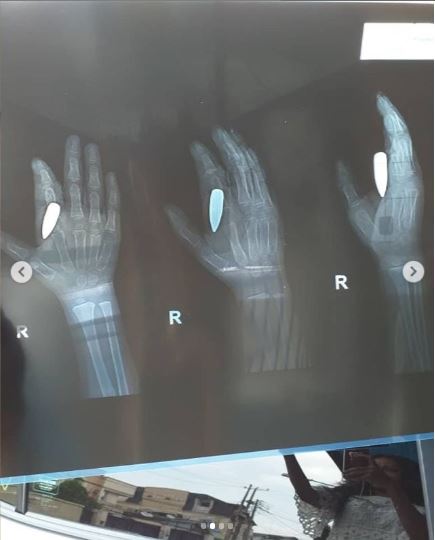

The boy's hand after he got struck with the bullet

An x-ray was carried out

"All these while we thought we were treating bone. Not until few days ago we decided to do a scan and we found out a stray bullet almost hit this boy somewhere else but instead of hitting somewhere else, it hit his hand.

"We just did a minor surgery yesterday and a bullet was taken out. It could only be God. God did this for us and we are forever grateful.